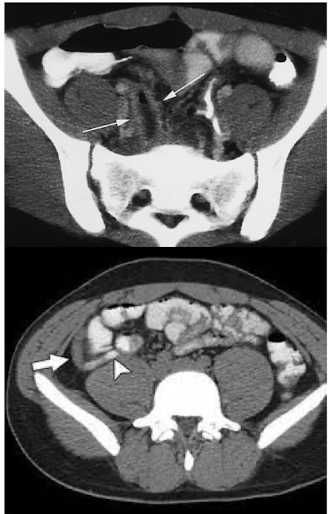

What is this and what type of scan

Appendicits, CT